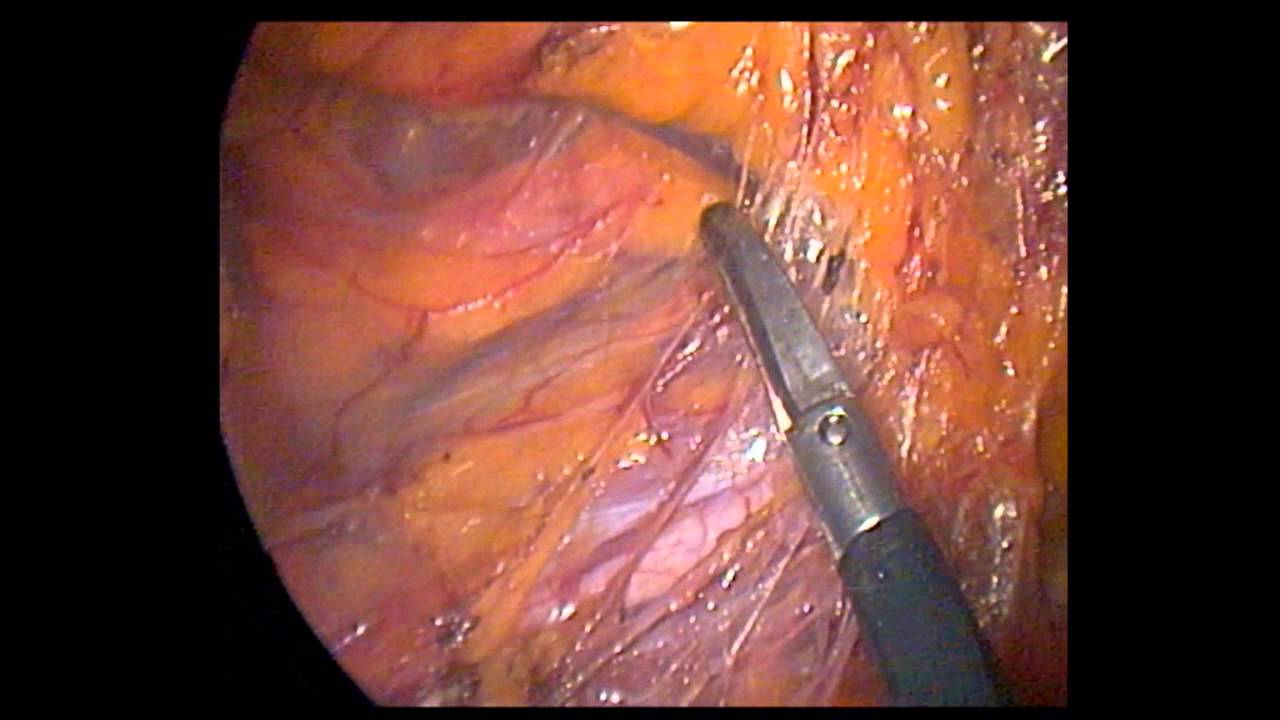

How do humans get infected? Learn about risk factors, symptoms, signs, diagnosis, stages, treatment, and prevention. There were 1,315 (62 percent) anterior resections and 821 (38. Malignant rectal tumors in cats are usually cancers involving lymph tissue (lymphosarcoma). Cancer can occur in almost any organ of the body. But when we see cancer in cats, it tends a: Each day, the researchers took nasal and rectal swabs from all six cats to assess them for the presence of the virus. The tumors that make up the other 15% include duct papillomas, sarcomas, and adenomas. Unfortunately, cats are notoriously good at hiding their conditions and symptoms. Studies reveal that 85% of mammary tumors in cats are malignant adenocarcinomas. Preventing the development of feline leukemia, either through vaccinations. Or give clues that may warrant a dr to inspect further for got endoscopy,whole abdomen color iv ct scan, whole abdomen ultarsound & all came ok except a. It is not contagious and cannot be spread from person to for example: